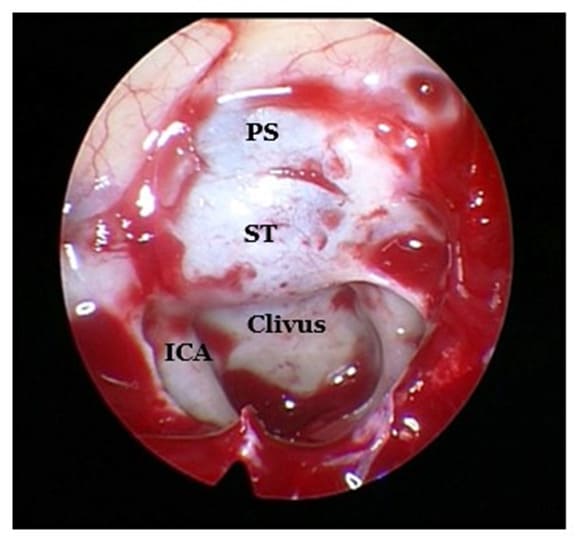

The lateral sinus wall contains noble structures. Often, the internal carotid artery (ICA) and the optic nerve (ON) can be identified bulging in the sphenoid cavity. In between there is the optico-carotid recess (OCR). In some cases, the maxillary nerve or the second branch of the trigeminal nerve (V2) and the Vidian nerve (V) may be recognized. The more pneumatized the sphenoid sinus, the more these structures are protruding. Therefore, they may be at risk during surgery, in case the surgeon is too posterior and lateral in the sphenoid cavity (3,12).

After removal of the bone covering the sella and the planum sphenoidale, access to the dura mater is gained. When the dura is opened, the following structures can be seen: The optical chiasma, the pituitary stalk, the sella, the basilar artery and the genu of the internal carotid artery (which might be close to the pituitary gland).

Figure 5: Endoscopic view during surgery showing the superior wall of the sphenoid sinus. Centrally, the bulge of the sella turcica (ST), anterior to it the planum sphenoidale (PS) and posterior to it the clivus. Lateral to the clivus, the paraclival portion of the ICA can be seen.